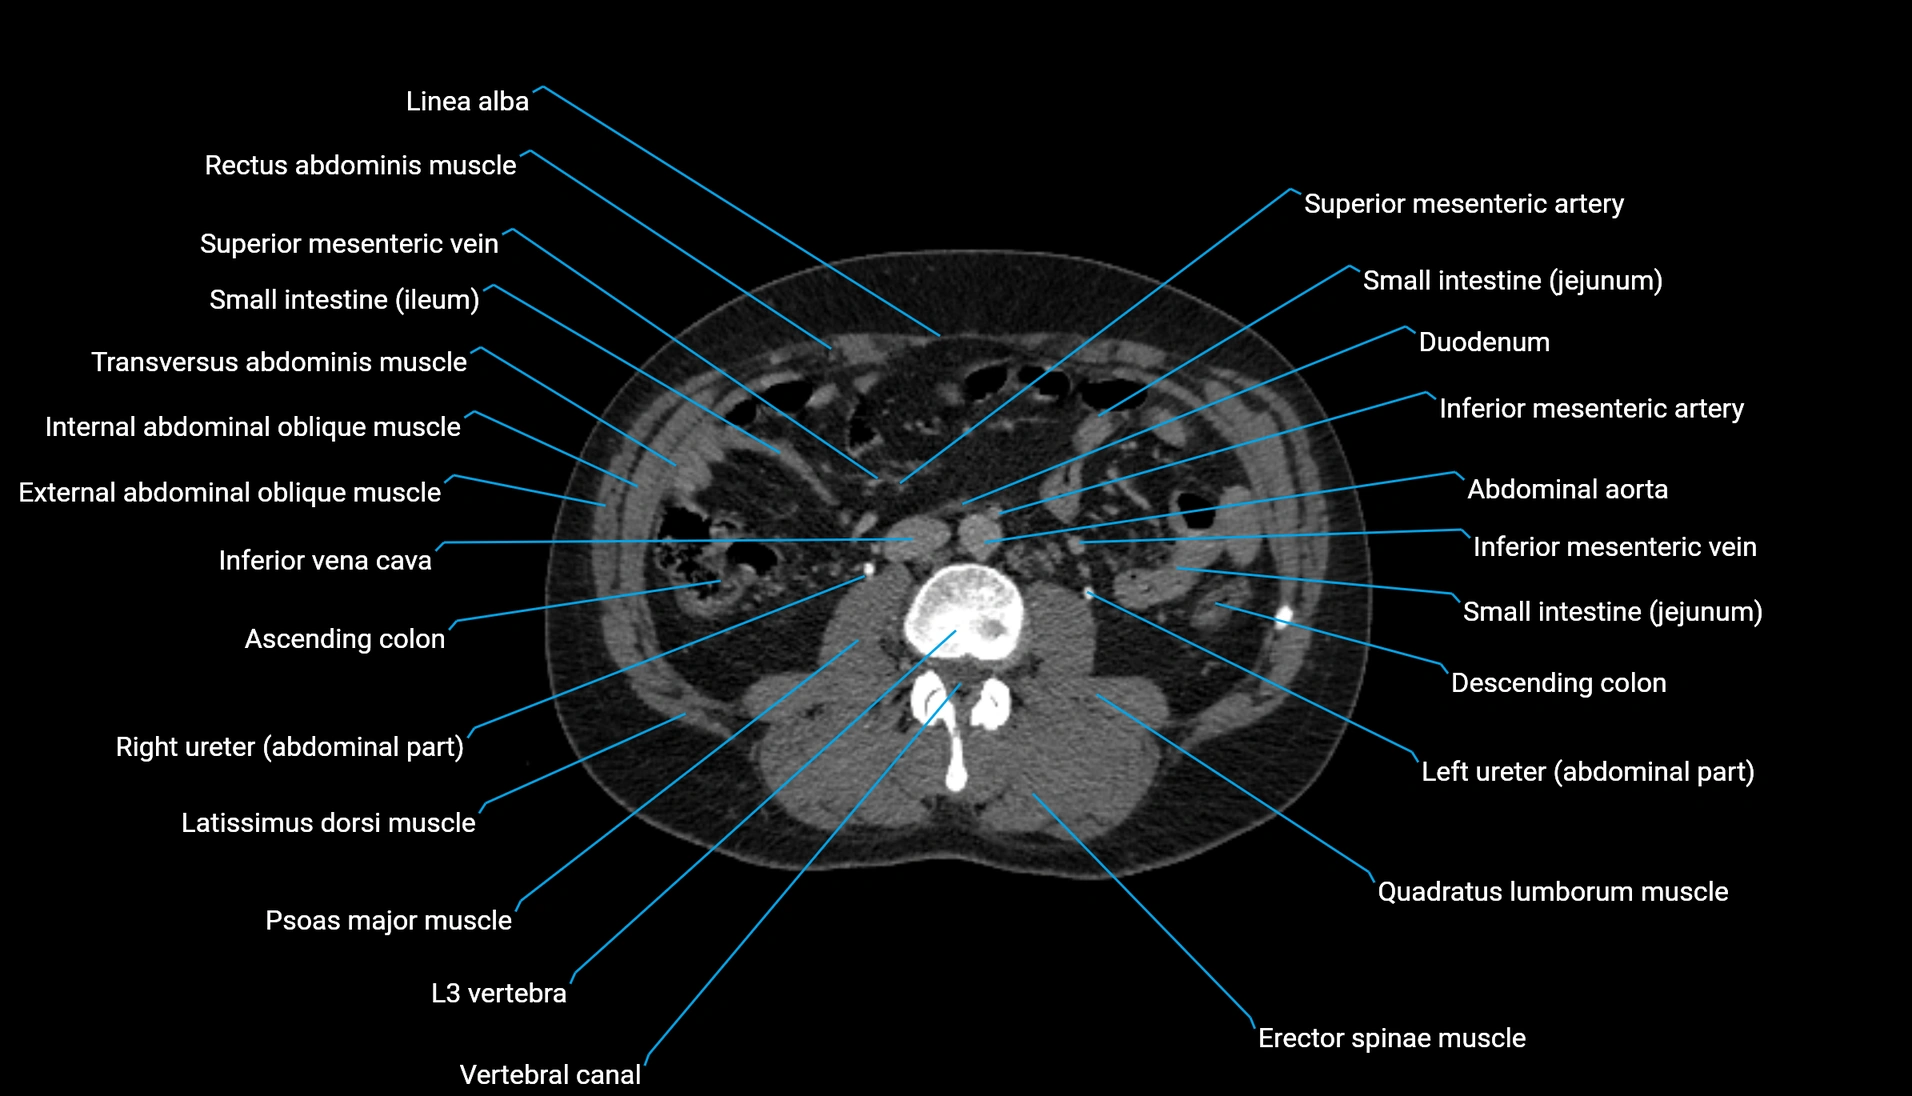

CT Appearance

Non-contrast CT:

-

Demonstrates cortical bone of acetabular rim in excellent detail

Detects fractures, dysplasia, retroversion, or bony overcoverage (pincer impingement)

3D reconstructions used in preoperative hip surgery planning

CT VRT 3D image

CT image